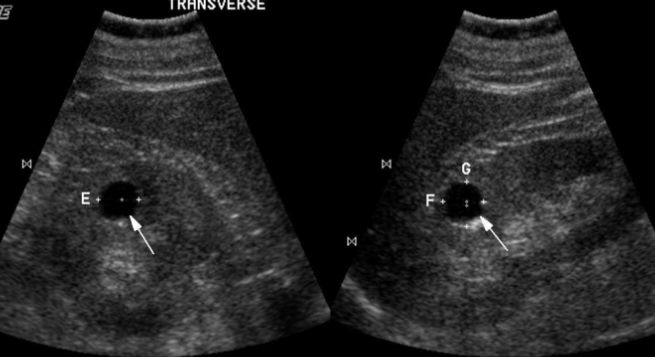

2 types of cystic disease placement

A

perirenal

subcapsular